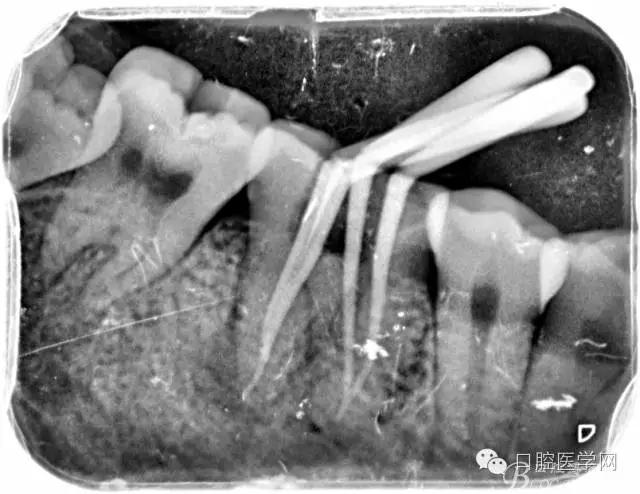

2、根管填充的界限

根管的解剖界限是从髓室根管入口到根尖部牙本质- 牙骨质交界处(生理性根尖孔) 。理想的根管充填应该是对生理性根尖孔冠方以上进行严密的三维封闭。临床上根据X线牙片判断根管充填的质量。牙片上充填材料与根管壁紧密接触一般被认为充填严密。关于充填止点,由于牙本质- 牙骨质界离根尖孔外表面平均距离为0. 5~0. 7 mm,同时相当多的根尖开口并不位于X线片的根尖处。因此临床上认为材料充填至距X线片牙根最尖端0. 5~1 mm (也有认为0. 5~2mm)为适填。

5、根管充填的技术方法

为达到更为理想的根充效果,研究人员和牙髓病医生一直在探索根管充填技术,并且发展出多种可供选择的方法。Ingle]将其归纳为3 类: ①“牙胶尖+封闭剂”式; ②“根尖1 /3充填”式; ③“注射或螺旋充填”式。目前临床广泛采用的主要是“牙胶尖+封闭剂”方式。按照充填压力的方向(侧向或垂直)不同和牙胶温度(冷或热)不同,根管充填有2 种基本技术:冷牙胶侧方加压充填和热牙胶垂直加压充填。现有的各种充填方法均是这2 种基本方法基础上的发展或改良。医生可根据方法的优缺点以及个人习惯选择使用。